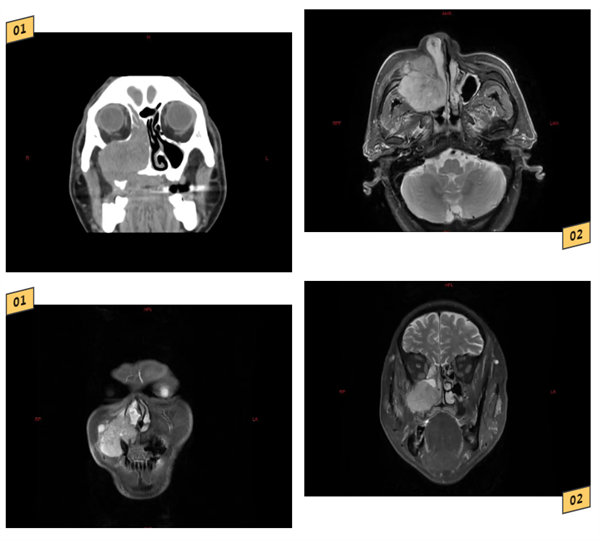

患者易先生(化名)出現(xiàn)“右側(cè)鼻阻、流涕伴右側(cè)頜面部腫脹2月”入院,行MRI、CT檢查后,結(jié)果顯示:右側(cè)上頜竇內(nèi)占位性病變,侵犯硬腭、牙槽骨、眶內(nèi)、翼腭窩;術(shù)前病理檢查結(jié)果提示:右側(cè)上頜竇高分化鱗狀細(xì)胞癌。